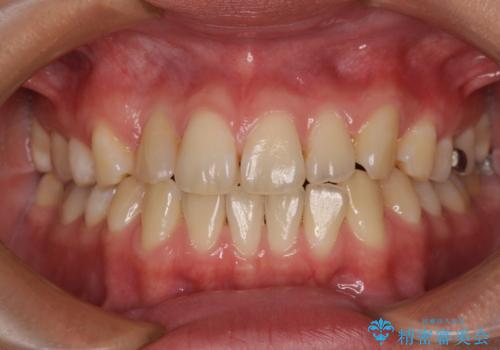

八重歯と乱れた咬み合わせを改善 ワイヤー装置での抜歯矯正

- 咬み合わせと、前歯のデコボコや八重歯、飛び出した口元を気にして来院された患者様です。

上顎は歯列不正が強く、右側臼歯部の咬み合わせは歯1本分ずれている状態でした。

補助装置を用いて奥歯の咬み合わせを改善しながら歯列を後方に移動させ、上下左右第一小臼歯を4本抜歯することで八重歯や口元の突出感を改善することとしました。

奥歯の咬み合わせの不正が顕著であったため、表側のワイヤー装置を選択して矯正治療を行うこととしました。

補助装置を併用したおかげでスムーズに奥歯の咬み合わせを改善することができ、我々も予想できないくらい理想的な仕上がりにすることができました。